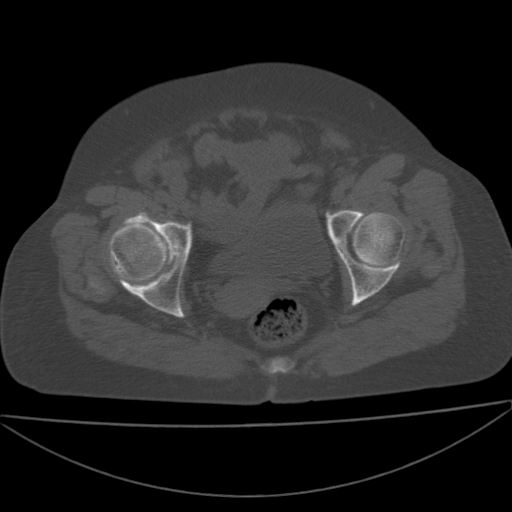

以下是引用王显瑞在2009-4-23 16:45:00的发言:[br]考虑股骨颈陈旧性骨折,股骨头缺血型坏死

以下是引用余辉在2009-4-23 17:08:00的发言:[br]考虑右髋关节退行性变.股骨颈改变考虑陈旧性骨折可能,股骨头顶部关节面下似有透亮区,股骨头皮质环增厚,考虑有股骨头坏死